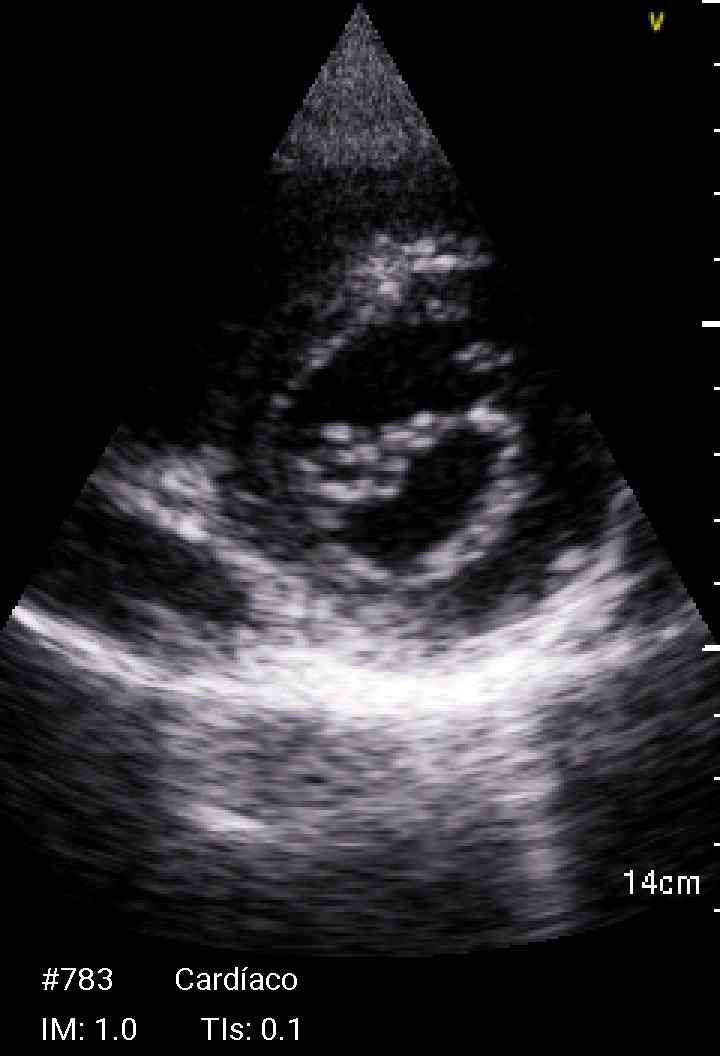

Ante la presencia de fiebre y soplo cardiaco se realiza ecocardioscopia.

Ecocardioscopia: Válvula mitral con engrosamiento de ambas valvas e imagen nodular no móvil en cara auricular del velo anterior (cambios degenerativos versus vegetación). Ventrículo izquierdo no dilatado ni hipertrófico, FEVI preservada. Ventrículo derecho normal. Mínimo despegamiento de hojas pericárdicas en cara posterior.